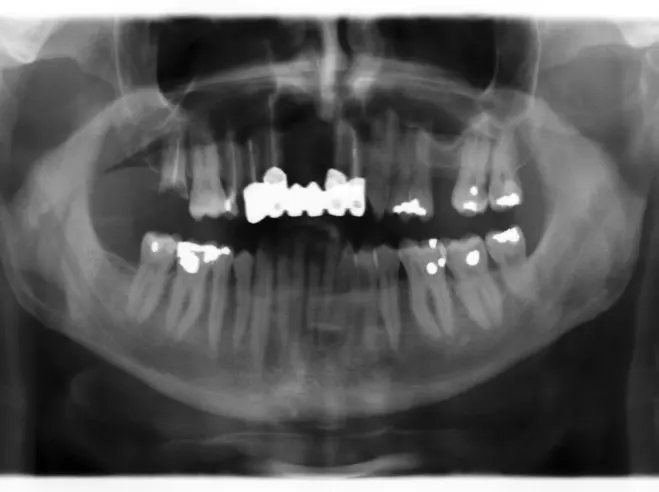

Nach dem Entfernen der insuffizienten Versorgung von 14 auf 22, stellten sich die Zähne 14, 13, 21 und 22 als nicht erhaltungswürdig heraus. Präoperativ wurde ein Eierschalenprovisorium gefertigt, welches im März 2015 auf den Zähnen 15 und 23 sowie auf temporären Implantaten regio 013, 014, 021 und 022 (Bone Trust® mini, Medical Instinct, Bovenden) intraoperativ angepasst und verankert werden sollte (vgl. Abb. 8-13). Im Verlauf des Eingriffs, bei dem die genannten Zähne operativ entfernt wurden, zeigten sich ausgedehnte radikuläre Zysten, die mit einer Resorption der vestibulären Knochenlamelle einhergingen und ektomiert werden mussten (Abb. 4-6).